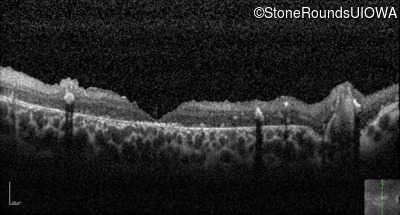

Optical Coherence Tomography - Left - 20/250 sc

Exemplar / OCT Stack